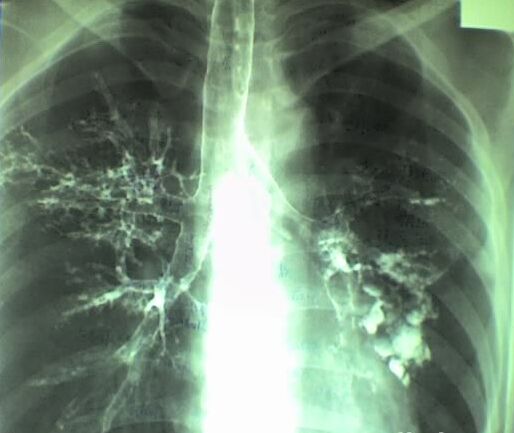

西安莲湖天颐堂中医医院专家指出,支气管扩张的主要致病因素是支气管的感染阻塞和牵拉,先天发育缺损及遗传因素引起的支气管扩张较少见。那么支气管扩张的危害有哪些呢?

随着支气管扩张的病情不断发展,毛细血管广泛破坏,肺循环阻力增加,可导致胸膜炎、脓胸、心包炎及肺源性心脏病,甚至心力衰竭等严重并发症。支气管扩张的典型症状是慢性咳嗽伴发大量脓痰和反复咯血。出现这些症状时都需要积极地进行治疗。